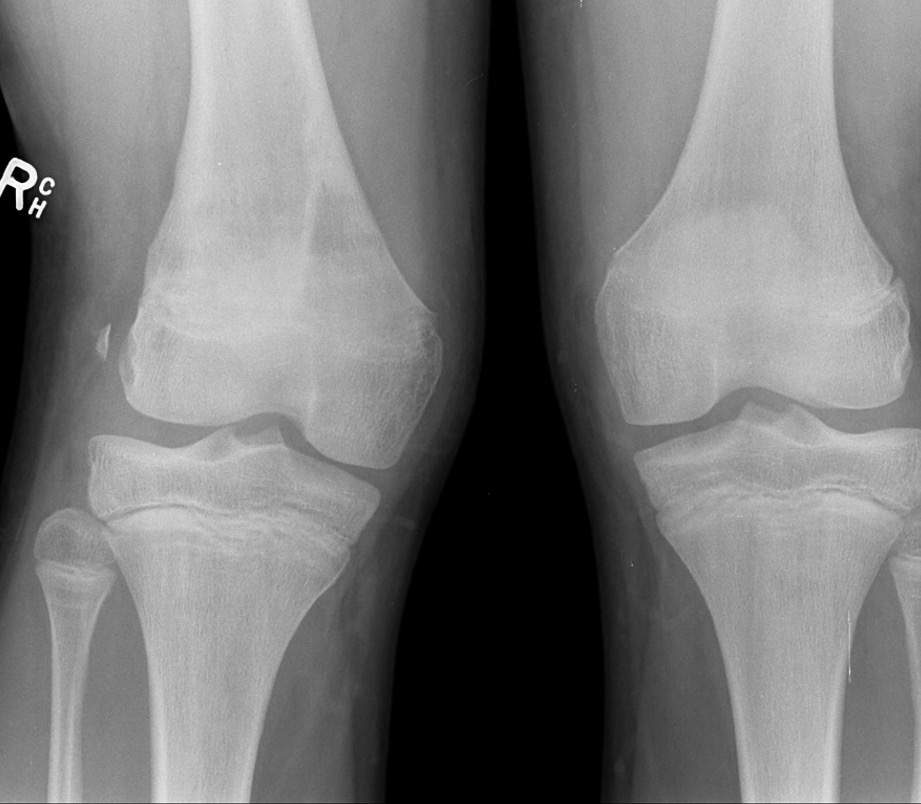

Growth plate fractures - Salter Harris Type II most common 60%

Distal Femoral Fracture SH2 APDistal Femoral Fracture SH2 Lateral

Salter Harris Type II